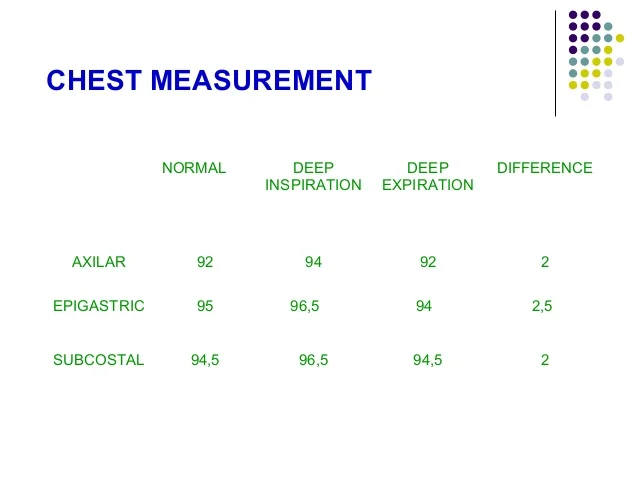

Chest expansion score which represents the circumference magnitude of the thoracic cage is used for a target when treating patients with respiratory disease It represents a scan performed with the patient on supine and images obtained at the end expiration It is a useful method for detecting small airways obstructive lung disease

Average Chest Circumference cm S D Download Table

Chest Measurement